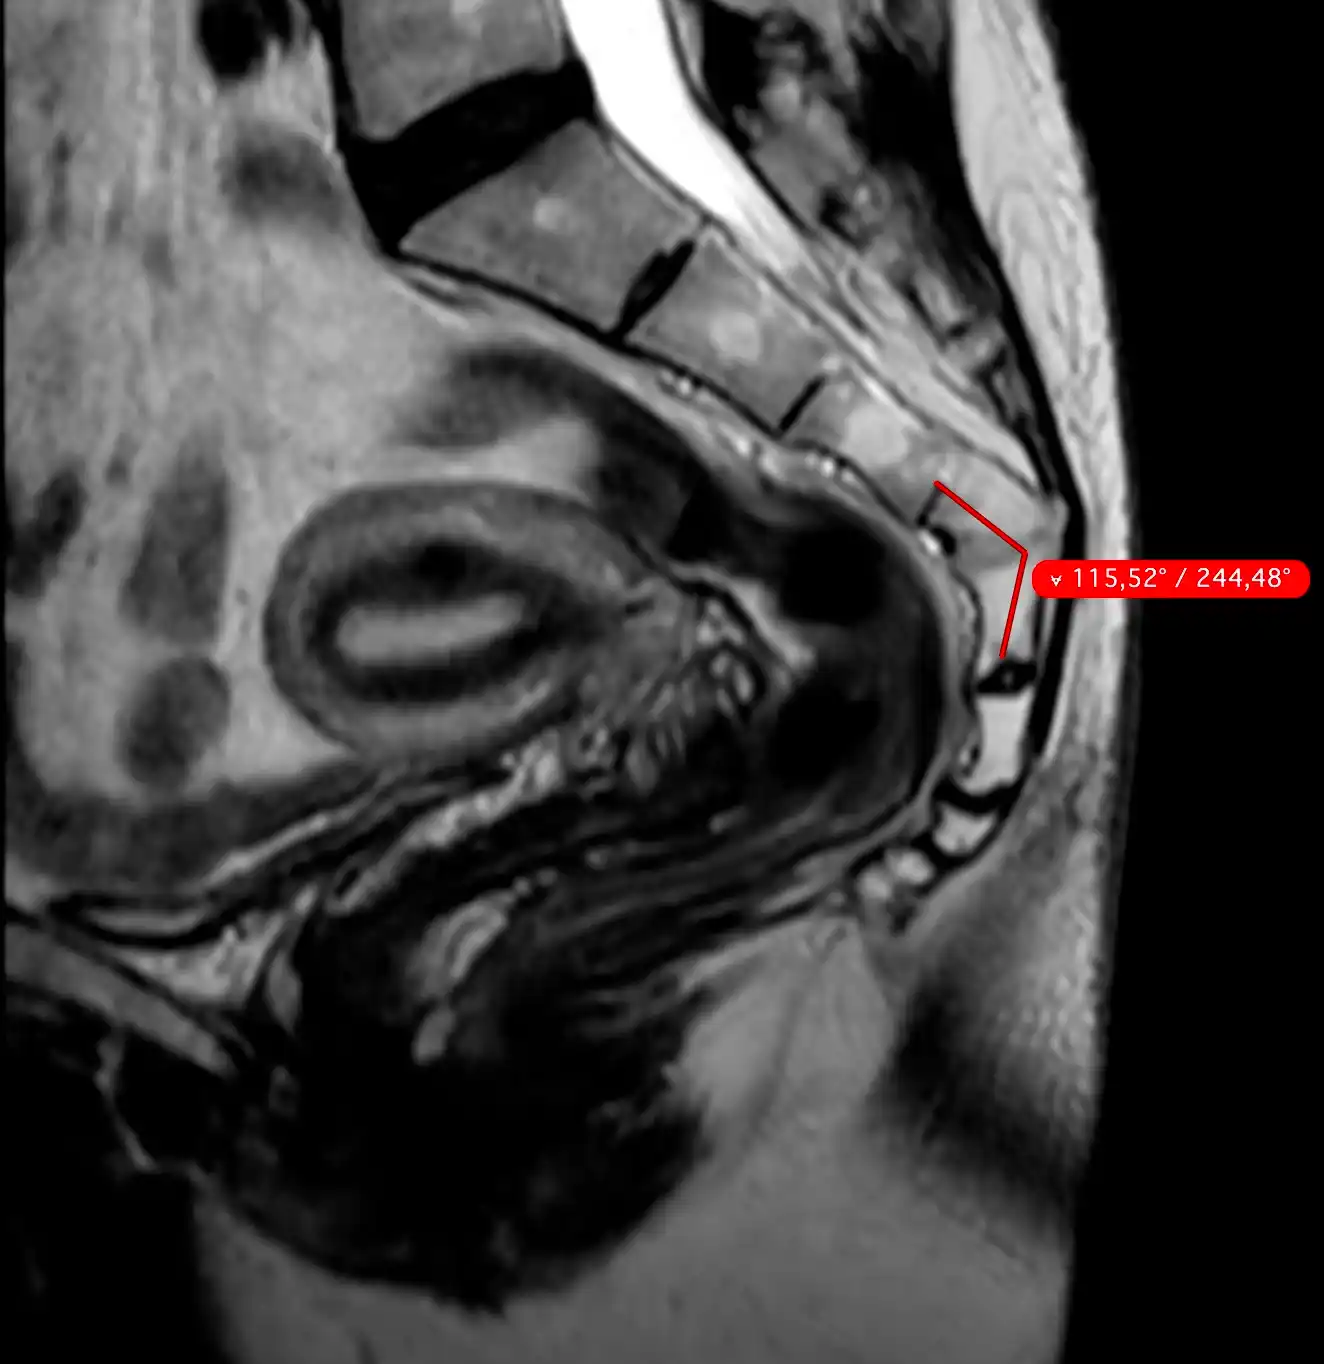

МРТ крижів і куприка — це сучасний та високоточний метод дослідження, який дозволяє детально оцінити стан крижової кістки, куприка, нервових структур, суглобів та навколишніх м’яких тканин.

Магнітно-резонансна томографія допомагає виявити причини болю в нижній частині хребта та області таза без використання рентгенівського випромінювання.